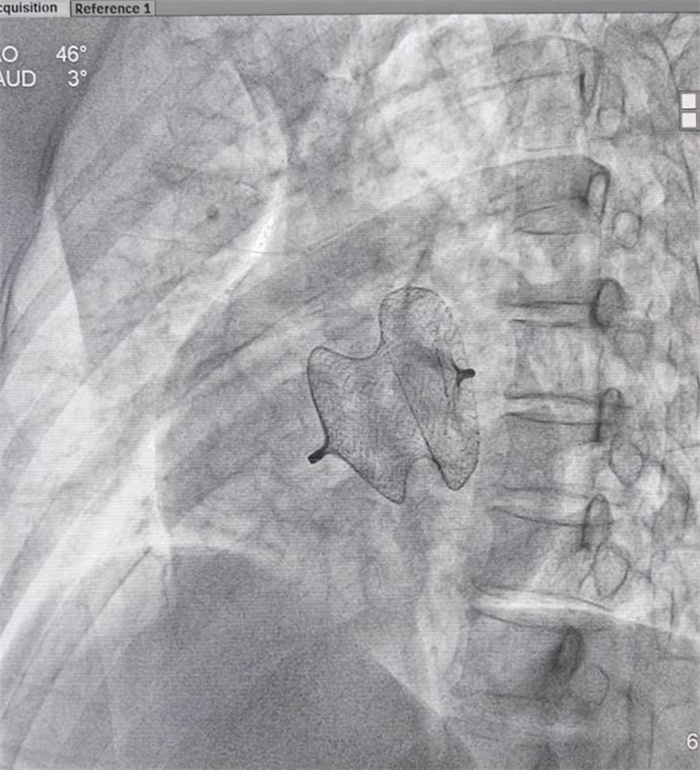

近日,在心血管內(nèi)科朱永彪主任的帶領(lǐng)下成功開(kāi)展了介入房間隔缺損封堵術(shù),這是西藏阜康醫(yī)院繼開(kāi)展冠狀動(dòng)脈支架植入術(shù)、起搏器植入術(shù)等手術(shù)后,心臟介入診療技術(shù)的再次突破。

一名中年女性患者,因“間斷心慌、氣促、水腫1年加重1周,反復(fù)頭暈”收治入院,診斷為先天性心臟病——房間隔缺損。經(jīng)進(jìn)一步詳細(xì)檢查心臟結(jié)構(gòu),確定了患者房缺最大直徑約30mm,左向右分流??紤]到患者年齡,合并嚴(yán)重肺動(dòng)脈高壓等因素,經(jīng)詳細(xì)術(shù)前討論認(rèn)為患者可以采取經(jīng)皮房間隔缺損封堵治療方案。征得患者和家屬同意后,7月26日為患者施行介入手術(shù)。

本次手術(shù)為微創(chuàng)手術(shù),患者術(shù)后10小時(shí)即下床活動(dòng),患者及家屬對(duì)手術(shù)結(jié)果非常滿(mǎn)意。此介入手術(shù)避免了傳統(tǒng)開(kāi)胸、體外循環(huán)等高風(fēng)險(xiǎn)因素。